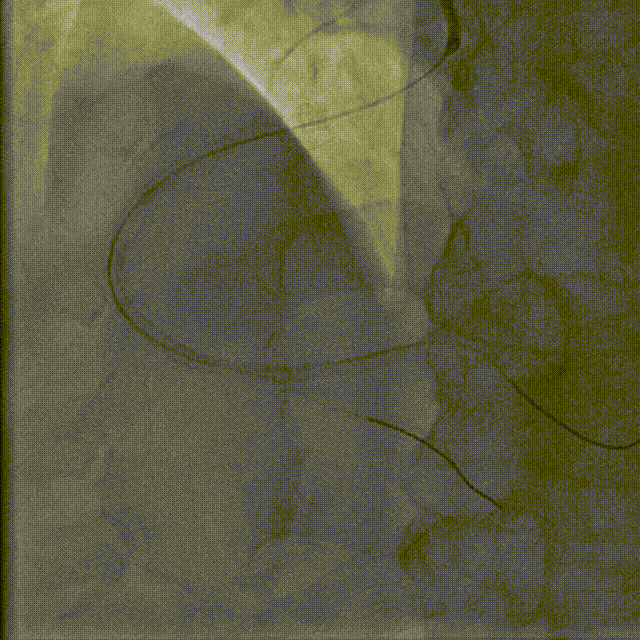

PCI术后结果及随访

远期结果:出院1月随访该患者目前病情控制良好,无不适症状。